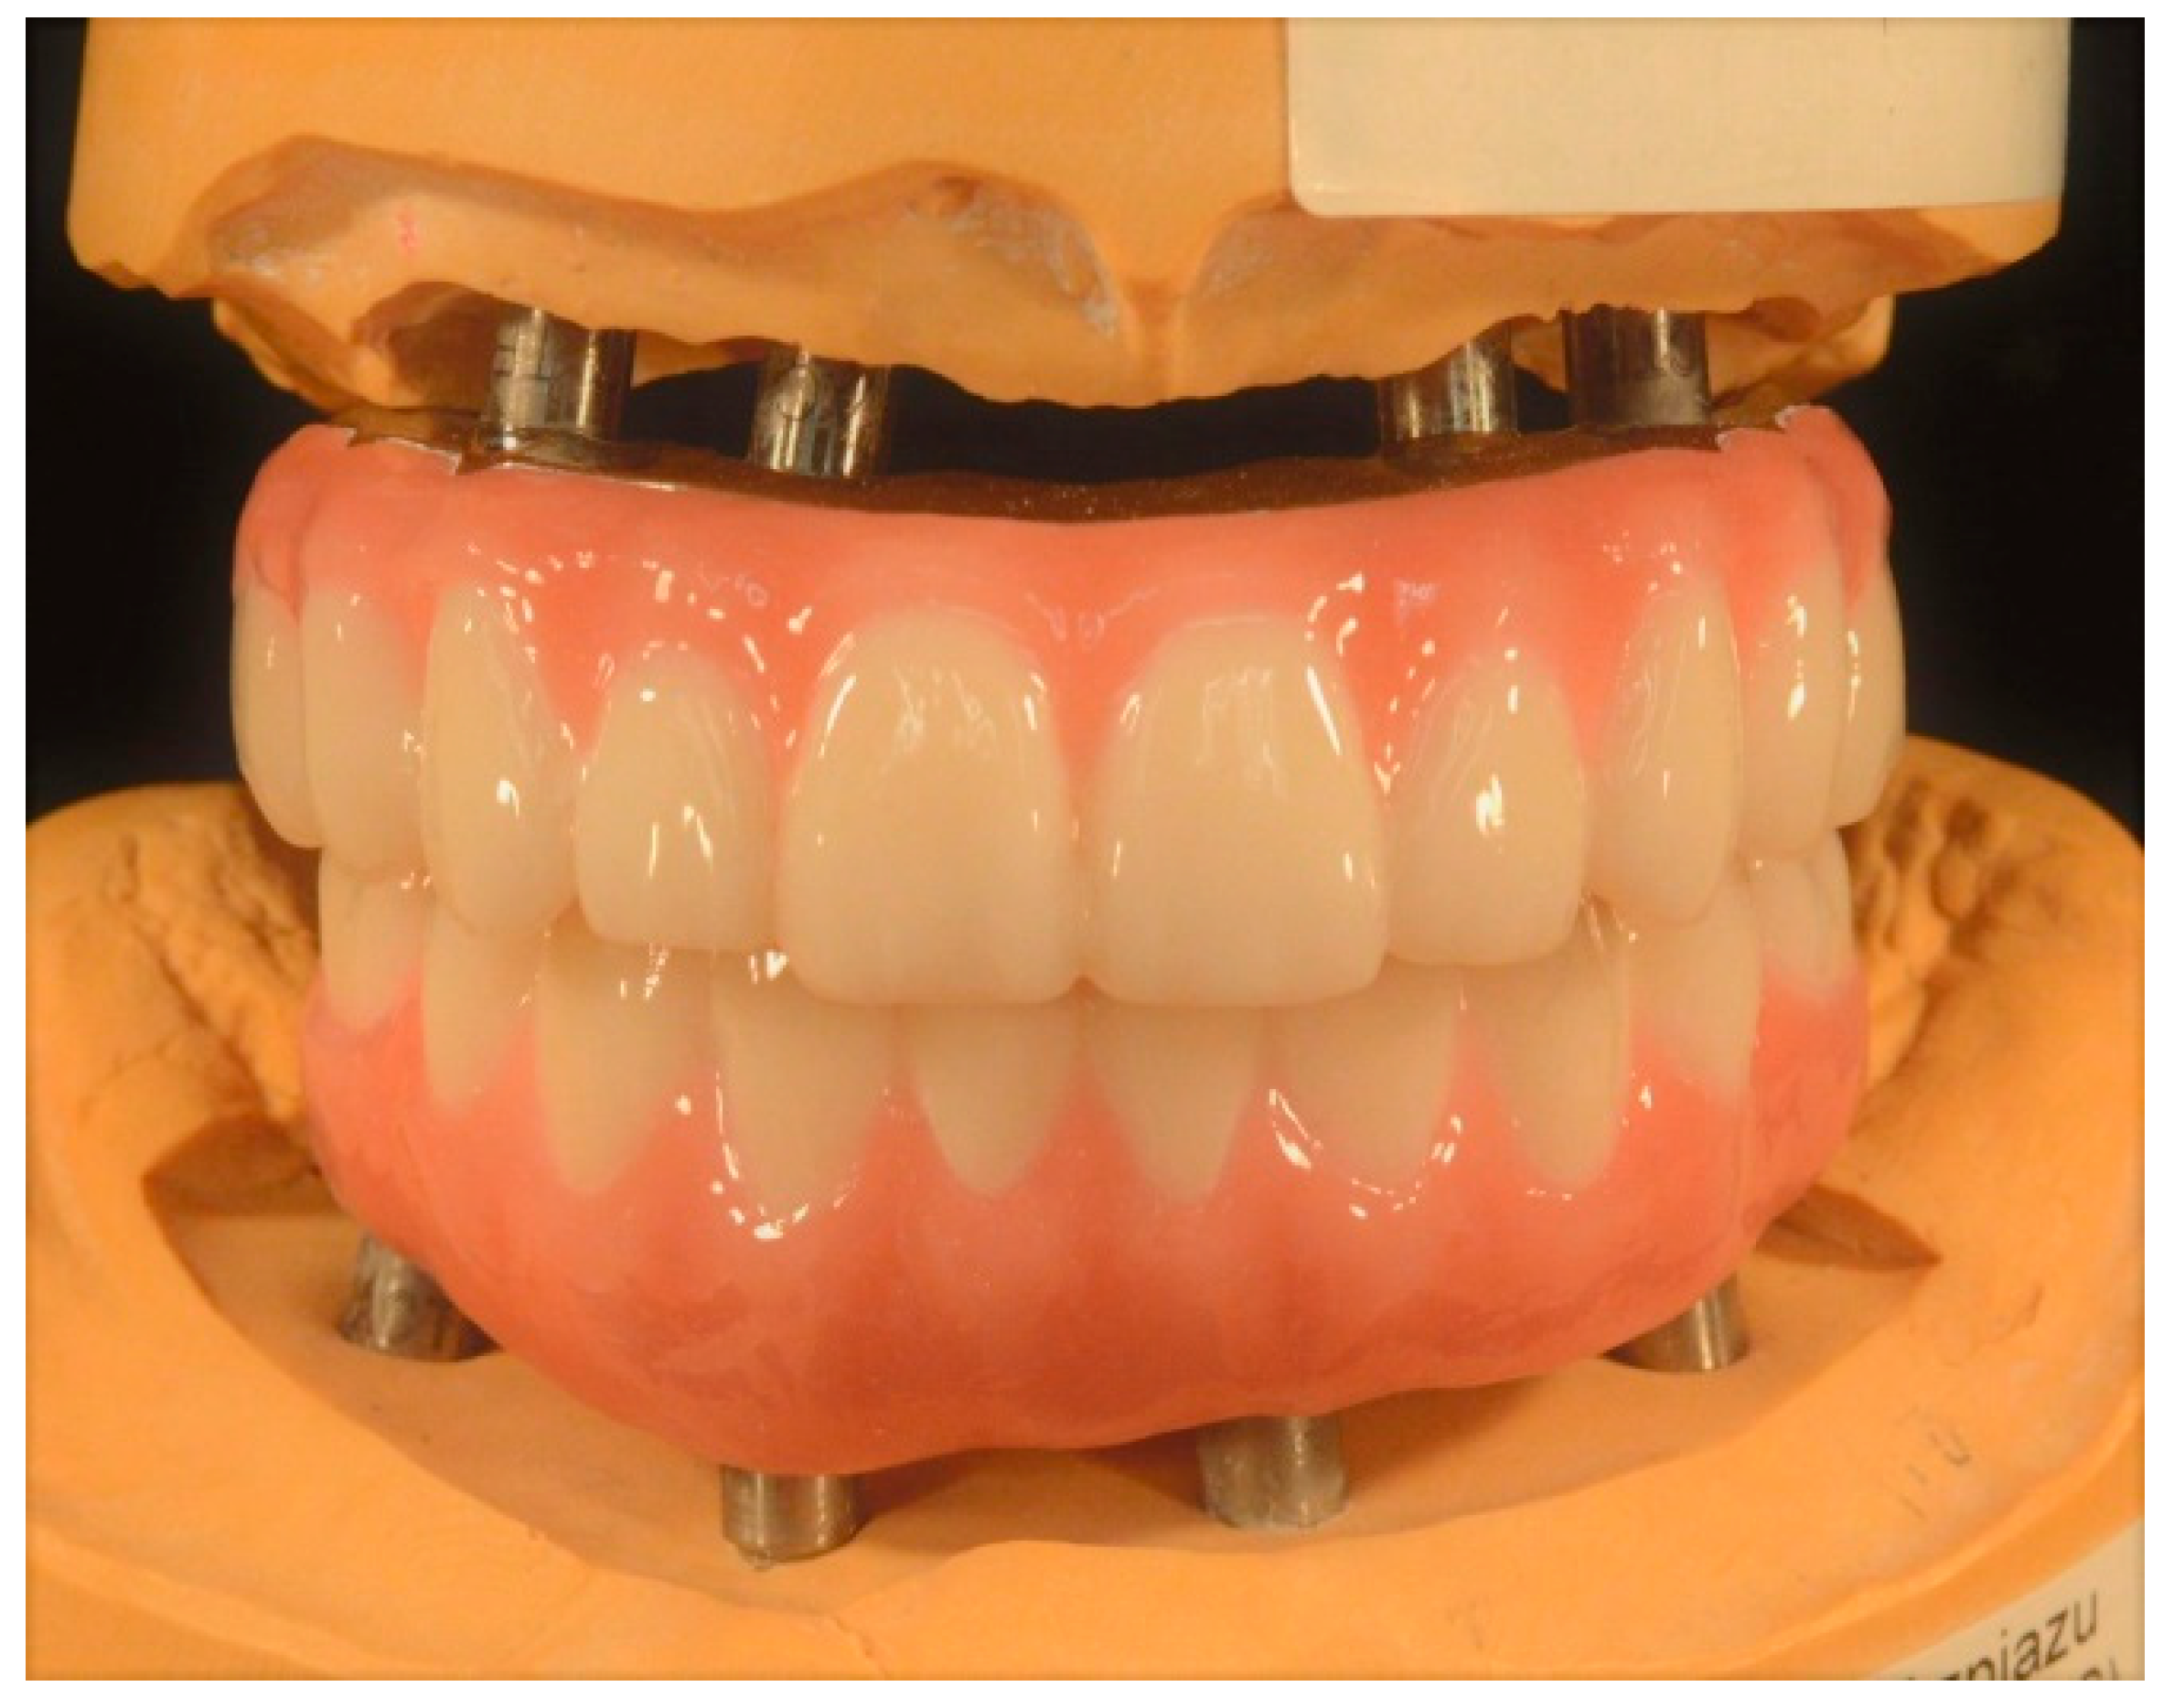

Subsequently, the definitive maxillary and mandibular prostheses were fabricated (Figure 9) and tried intraorally.

Figure 9.

Maxillary and mandibular definitive complete-arch implant-supported prostheses.